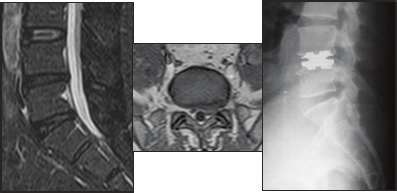

Fig 1.a & Fig 1.b - Kyphosis with severe cervical myelopathy. Fig 1.c - Anterior multilevel corpectomy and reconstruction.

Fig 4.a & Fig 4.b - Discogram positive at L4-L5 and at L5-S1. Fig 4.c - Lumber disc replacement at L4-L5 with ALIF at L5-S1V